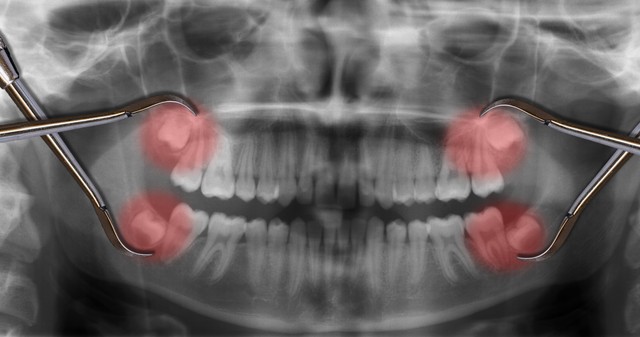

智齿是人们最后长出来的一颗牙齿,现在人们由于进食比较精细,骨量与牙量之间关系不调。导致智齿萌出空间有限,很多人智齿都长得歪七扭八。

智齿的位置将决定拔牙的难易程度,有些智齿位置较低,需要翻瓣手术才能将其拔出。此时,拔牙的风险也会增大,更容易出现较严重的创伤肿胀反应。一不小心,可能脸就会肿成包子。不过,此情况最多持续3~5天,便可消退,不会对身体产生大的伤害。